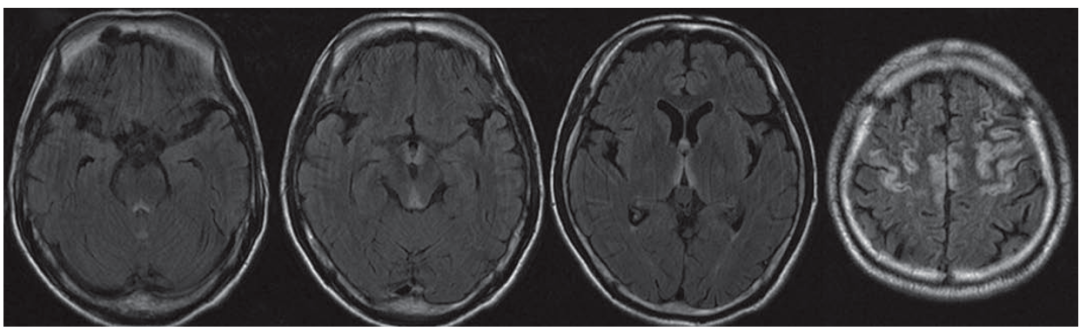

脑白质脱髓鞘

表现为皮层下白质及侧脑室周围多发点状或斑片状长Tl、长T2信号,可以与其他类型影像学损害并存。临床表现为精神障碍、行走困难、肌张力高、病理征阳性等。

以上影像学改变可单独亦可多种共存。